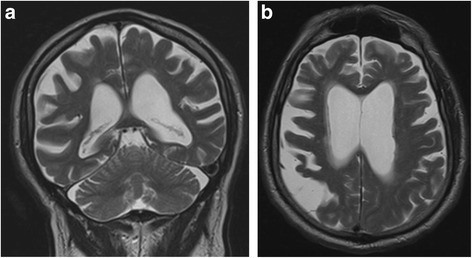

Blodprop i hjernen

Når en person rammes af en blodprop i hjernen og mere specifikt i hjernens motoriske cortex, kan det medføre lammelser af bestemte muskler. Da nervebanerne fra cortex krydser over i modsatte side i bunden af hjernen, vil en skade i venstre side af motorcortex give lammelser i højre sides muskler.

Ud over skader i motorcortex forårsaget blodpropper har det vist sig, at skader i områder, som ligger på ydersiden af thalamus, de såkaldte basalganglier, også kan give problemer med motorisk indlæring.